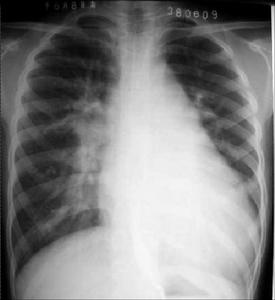

先天性心臟血管病 X線表現心臟導管檢查以及與之相結合進行的選擇性指示劑稀釋曲線測定和選擇性心血管造影,通過各心腔內壓力的測定和血標本氧含量的分析,向各心腔注入指示劑觀察其稀釋情況,注射造影劑觀察造影劑的流動和心血管腔的充盈顯影情況,可以比較直接地了解本病病人的病理生理和病理解剖改變,有確診和鑑別不同類型先心病的價值。